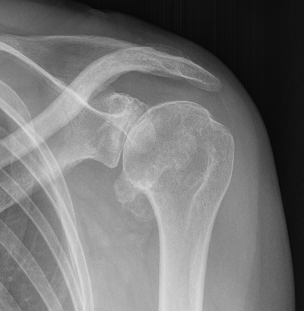

Samilson-Prieto

Grade 2 Grade 3

Grade 1: Osteophytes < 3 mm

Grade 2: Osteophytes 3 - 7 mm with slight narrowing GHJ

Grade 3: Ostephytes > 7 mm with GHJ narrowing and sclerosis